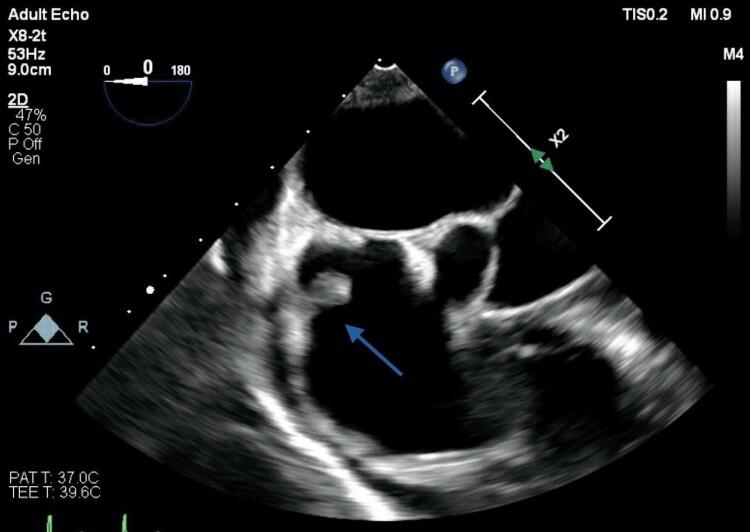

A 59-year-old man with a history of metastatic duodenal carcinoma was admitted with a 2-week history of fever and rigors. Inflammatory markers were elevated and blood cultures positive for . Transoesophageal echocardiography performed to investigate for infective endocarditis revealed a 2.3 cm long, thin fibrous band attached to the posterior mitral annulus and extending to the base of the middle scallop of the anterior mitral valve leaflet causing localized tethering, but no valve dysfunction. The band was felt to represent a bystander anatomic variant unrelated to the sepsis, which was most likely gastrointestinal in origin. The patient responded well to intravenous antibiotics.

一名有转移性十二指肠癌病史的59岁男性因发热和寒战2周入院。炎症指标升高,血培养阳性。为调查感染性心内膜炎而进行的经食管超声心动图检查显示,一条2.3厘米长的细纤维带附着于二尖瓣后环,并延伸至二尖瓣前叶中间扇贝形瓣叶的基部,导致局部受限,但无瓣膜功能障碍。该纤维带被认为是一种与脓毒症无关的旁观者解剖变异,脓毒症很可能起源于胃肠道。患者对静脉使用抗生素反应良好。